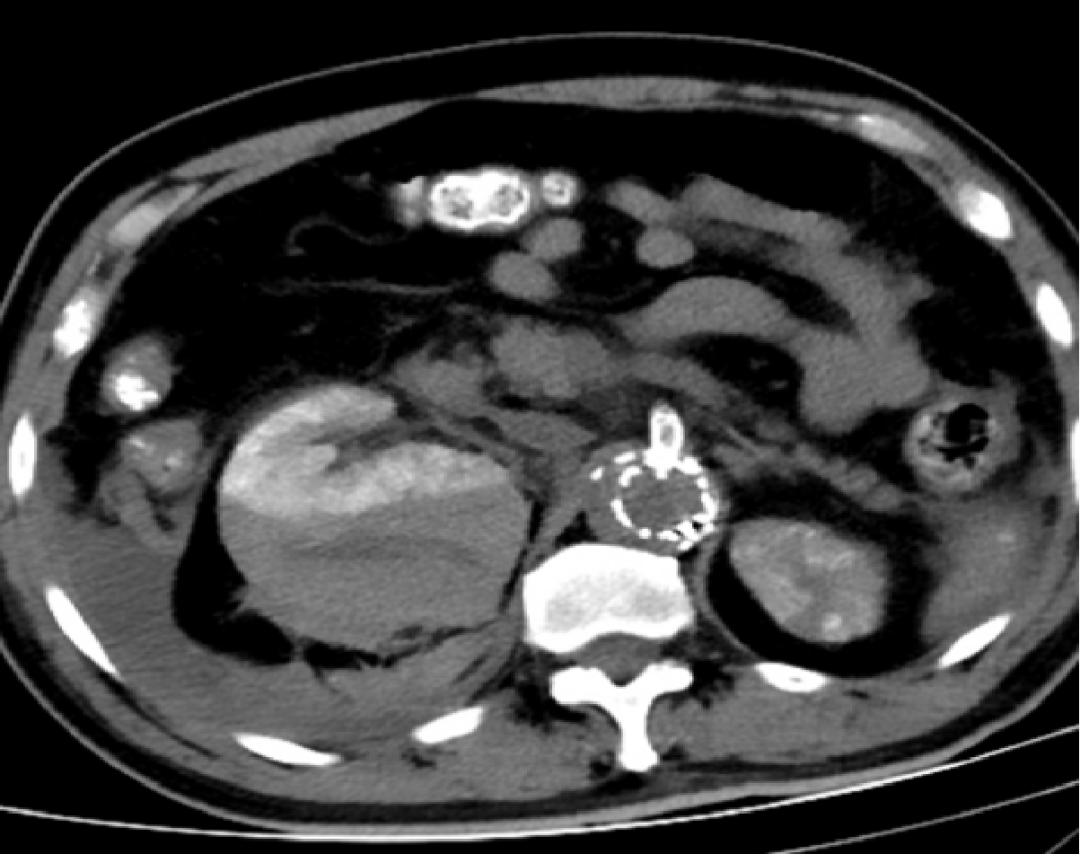

病例:包膜下血肿

术后第二天:腹胀,血常规:血色素10.4g,肾功能指标稍高

术后第三天:血压下降85/50mmHg,心率增快,胸闷加重。血常规示血色素7g,肾功能异常。CT右肾包膜血肿,后腹膜血肿